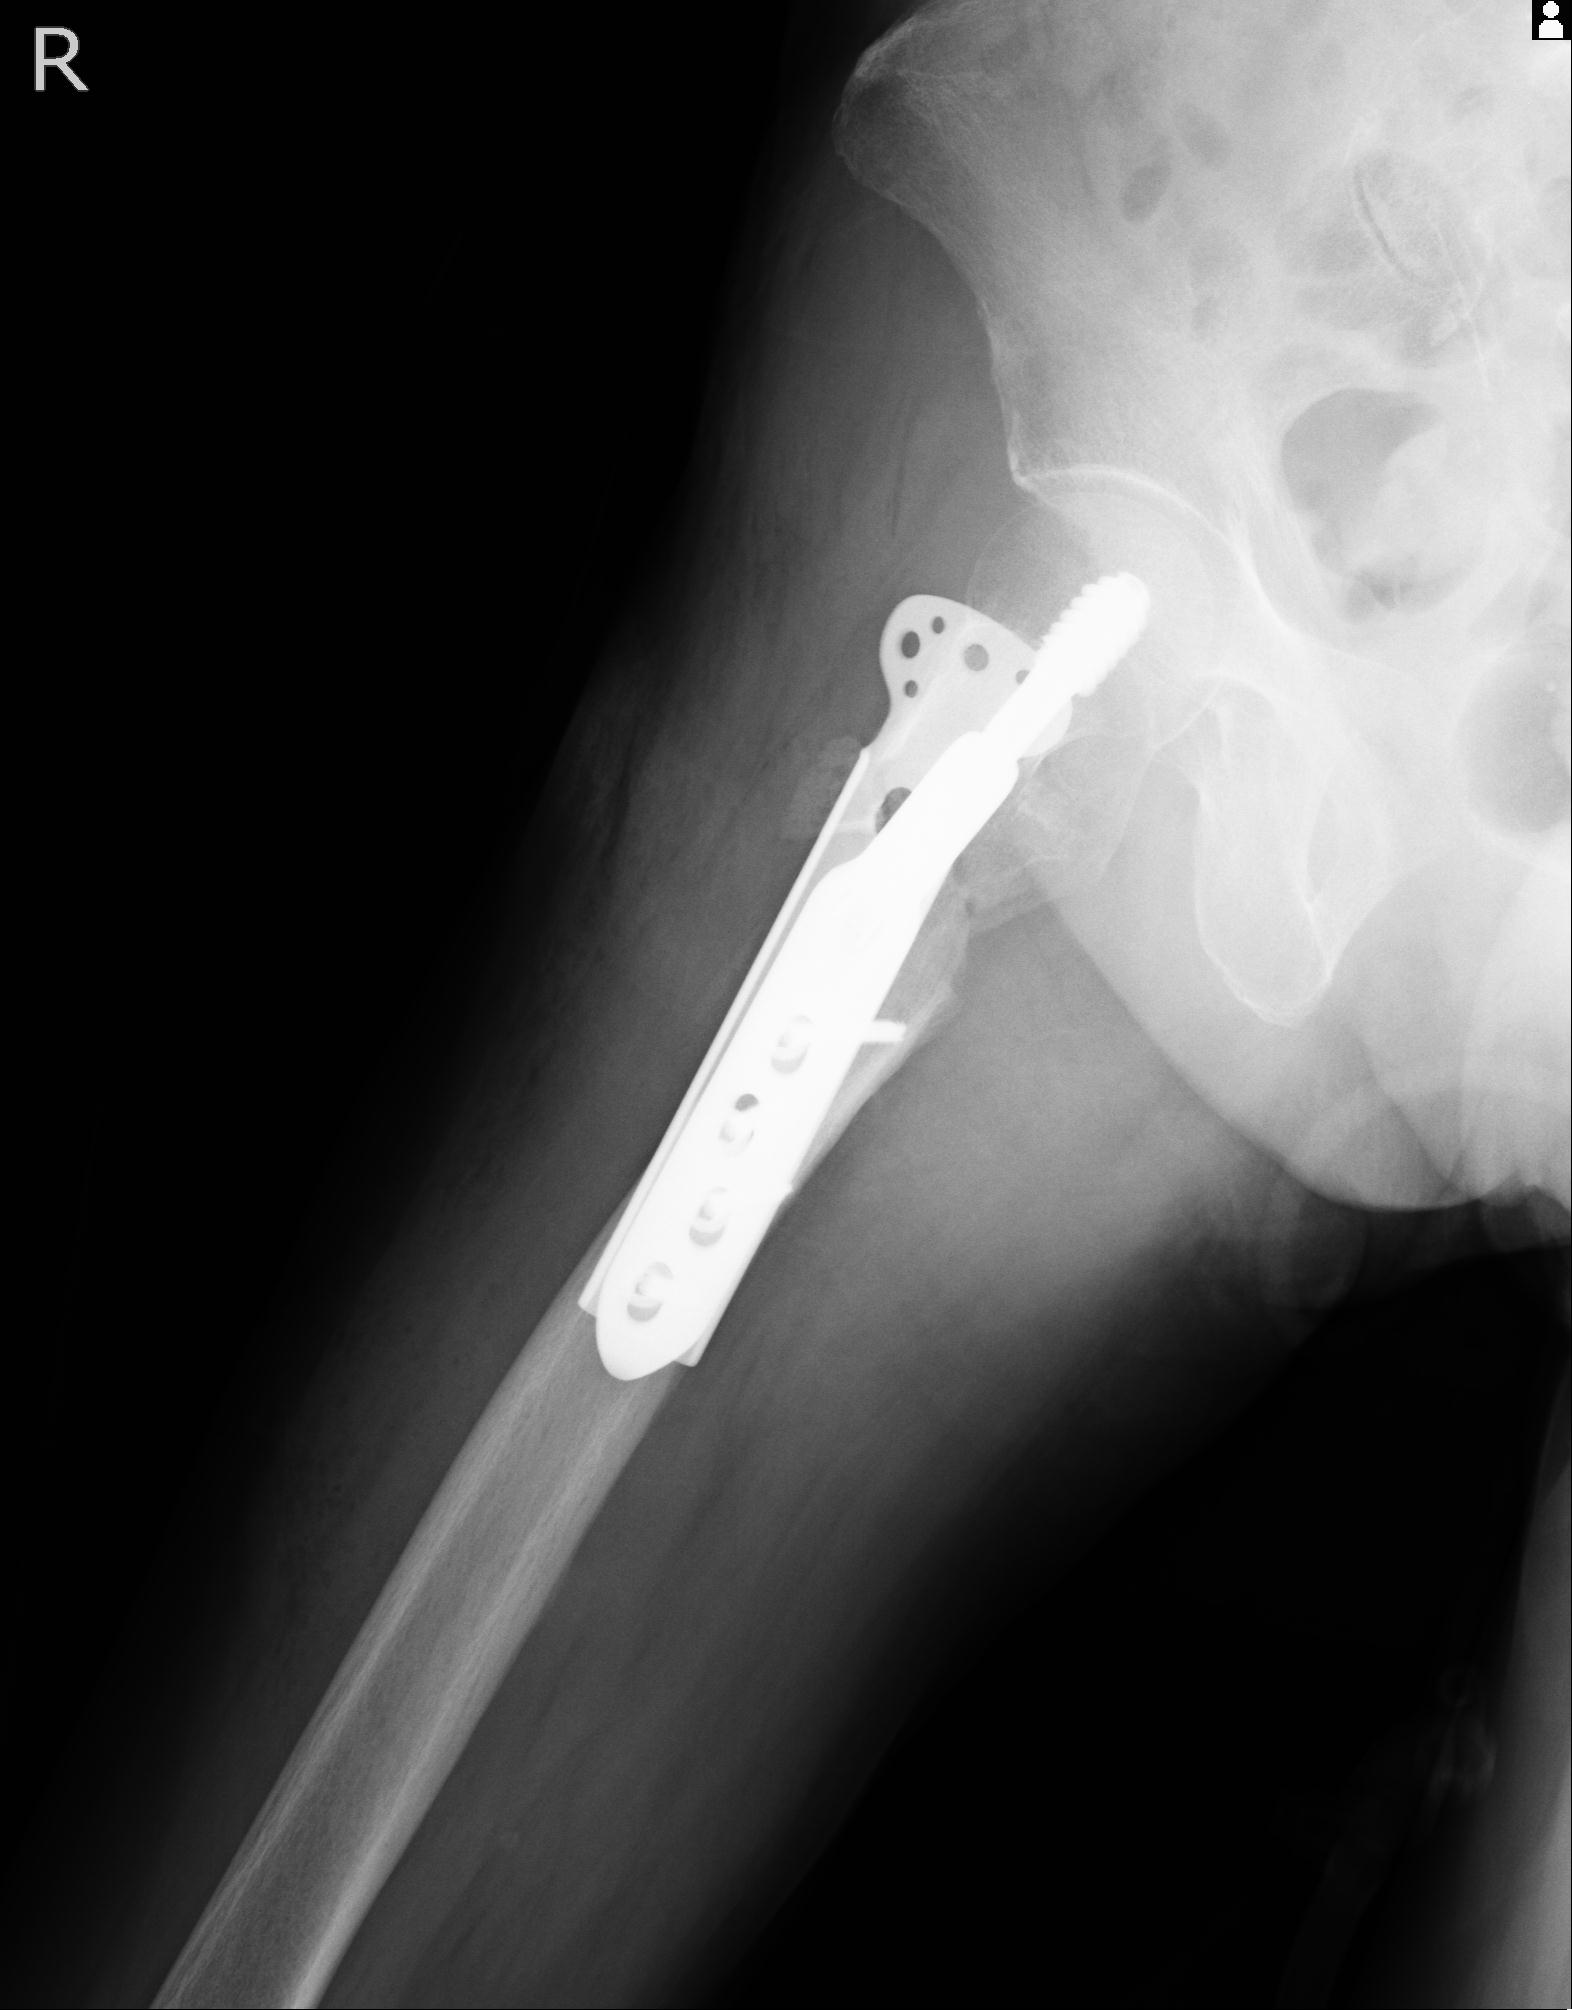

46666 1/28 両股正面+軸と 1/26 右手関節 2R 76歳女性 右転子部骨折

102811 1/13 股関節 2R 1/19 2R 80歳女性 右DHS